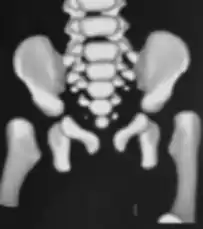

MRI- bilateral dislocation of hips, epiphyseal core (small arrow), and dysplastic acetabulum (large arrow) -

CT hips -

X-ray- dislocation of hips